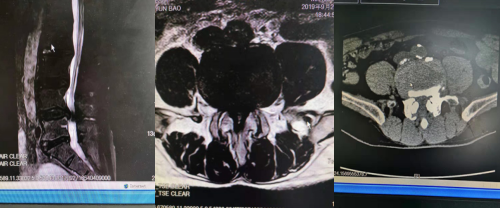

一、术前影像学资料

(腰椎DR片)

术前核磁及CT检查